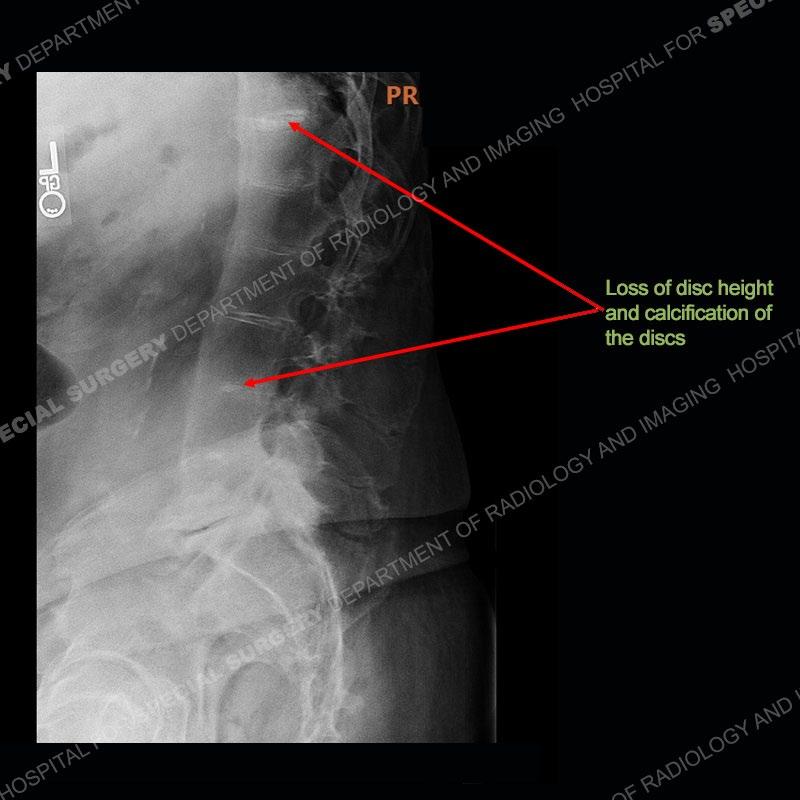

There is severe degenerative change of the left hip. The lumbar and thoracic spine show calcification of the intervertebral discs, loss of disc space, and bulky bony bridging across the disc spaces. Of important note is that the sacroiliac joints are open. They show advanced degenerative changes but not findings of an inflammatory arthritis. Bilateral knee arthroplasties are present and there are severe degenerative changes of both glenohumeral joints.

A rare metabolic disease also termed alkaptonuria. It results from a lack of homogentistic acid oxidase which results in a build up of this metabolite which gets deposited and oxidized in multiple tissues including, cartilage, synovium and bone. The soft tissues of the joint inclusive of the cartilage and the synovial fluid can be stained a black color or be densely black. Additionally, the urine can be stained black accounting for the term alkaptonuria. These patients frequently present with early onset osteoarthritis of multiple joints. There is classically calcification of the discs and a loss of disc space height. As patients get older, there may be bony bridging across the disc spaces as bulky paravertebral osteophytes.

In comparison to ankylosing spondylitis (AS) where there are thin syndesmophytes of the outer annulus, this bony bridging tends to be bigger and bulkier. In addition, at this stage of AS the sacroiliac joints would be fused, but in ochronosis as seen here, the SI joints are open although with severe degenerative changes. No erosions are present of the SI joints, just advanced degenerative changes. This patient was treated with a left total hip arthroplasty and the black deposition of oxidized homogentistic acid of the cartilage is well shown.